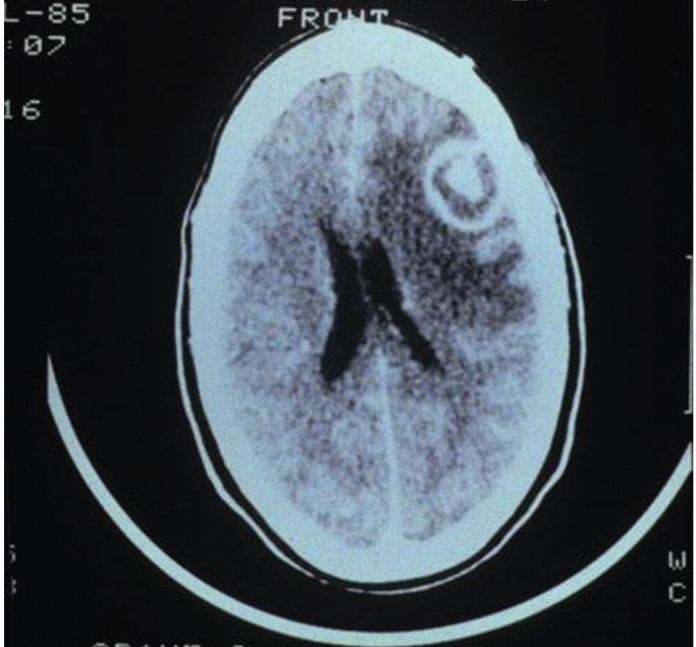

Advanced HIV infection can lead to opportunistic infections of the brain and spinal cord. Well-known pathogens include Toxoplasma gondii, Cryptococcus neoformans, and JC virus. Primary central nervous system lymphoma may also affect severely immunocompromised patients. Infections and malignancy cause variable neurologic symptoms, usually reflecting the location and severity of disease.

For example, patients with solitary lesions often present with headache or focal deficits, whereas patients with increased intracranial pressure from substantial masses (with or without edema) may have visual disturbances, nausea, or altered consciousness. Patients with meningitis or encephalitis generally present with one or more of the following: fever, headache, neck pain or stiffness, altered mental status, or seizure. Symptoms of myelopathy include weakness and sensory changes; upper motor neuron signs, such as spasticity and hyperreflexia, may also be found.

Head computed tomography depicting a ring-enhancing lesion in a patient with central nervous system toxoplasmosis.